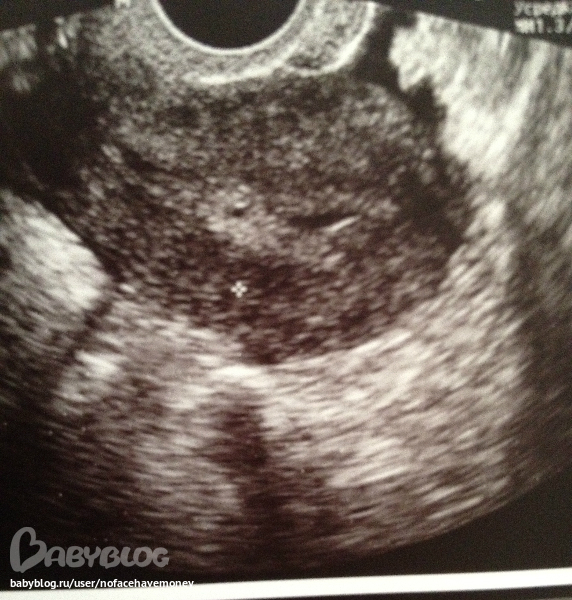

затем мы с ней прошли к узисту и вот смотрите какое заключение(((

пока особо не видно плодного яйца, но что то есть-но не поймут то ли плодное яйцо то ли нет

на фото видна точечка ,вы видите ?узист сказала если это беременность-то плодное яйцо слишком снизу находится чуть ли не рядом у входа шейки матки